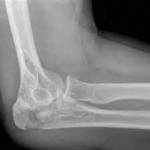

Из инструментальных методов исследования обычно привлекают рентгенографию локтевого сустава и дистальных отделов плечевой кости, чтобы исключить другие патологии, манифестирующиеся такими же болями и нарушением движений. При подозрении на поражение нервных веток может потребоваться электромиография – ее проводят для изучения нервной проводимости.